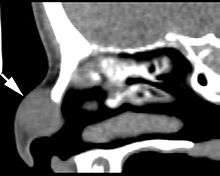

Imaging findings

Imaging studies are performed before surgery or biopsy to preclude an intracranial connection. Images usually show a sharply circumscribed but expansile mass. It may be difficult to exclude the intracranial connection if the defect is small whether employing computed tomography or magnetic resonnance.[1]